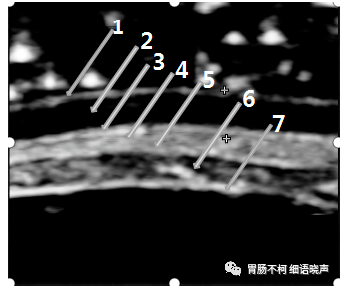

超声七层图示部分病例层次来源(图片来自我的课件):

病例一,自黏膜上皮线起始至肿块,胃壁超声七层显示了强(LI)-低(L2)-强(L3)-低(L4)-强(部分L5)五层线,强烈提示肿块跟L5(黏膜下层)关系密切,结合肿块长轴与胃壁长轴一致的特点,超声首诊胃淋巴瘤,病理免疫组化结果证实:

病例二,超声胃壁七层不显示、只显示五层时,自黏膜上皮线起始至肿块,胃壁五层显示了强(L1)-低(L2)-强(L3-5)三层线,强烈提示肿块跟L6(固有肌层)关系密切,结合混杂回声特点,诊断为间质瘤:

病例三,胃体前壁位于黏膜下层的异位胰腺,其前后均可见L5(黏膜下层)的部分强回声线,呈“黏膜下层分离征”:

病例三,十二指肠球部的平滑肌瘤,内部极低回声,其两端与L6(固有肌层)延续,提示L6(固有肌层)来源:

病例四,直径9.5cm的肿块,腔外型生长,放大图片清晰显示2.0cm左右的蒂与胃壁L6(固有肌层)相延续,结合形态及回声特点,超声首诊高危险度间质瘤,术后病理证实: